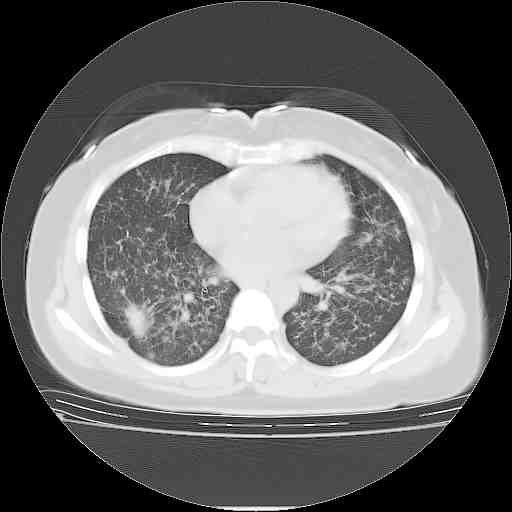

下面是今天刚刚做的,在上海治疗,吃了家属也说不清的一种药,一个月1万左右,

考虑  腺癌肺内转移,治疗较前病灶缩小、减少

肺癌并肺内转移,这种疾病治疗后在影像上看略有好转,不是很显著,但是肿瘤治疗效果影像只是一方面。

支持肺癌并肺内淋巴管炎,  原发灶小了,但转移较前片明显了.

支持右肺下叶周围型肺癌并肺内淋巴管炎,  原发灶小了,但转移较前片明显了.。

支持右肺下叶周围型肺癌并肺内淋巴管炎;病灶有所控制。

标准的癌性淋巴管炎!!距大去之日不远已.

支持右肺下叶周围型肺癌并肺内淋巴管炎,  原发灶小了,但转移较前片明显了.